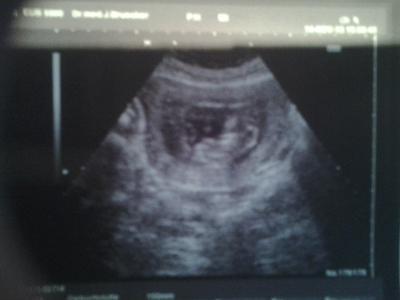

Hallo zusammen, ich muß mich entschuldigen, ich hatte total vrgessen meinen Bericht zu shreiben...... Im Moment ist alles etws durcheinander bei mir, hoffe ich kriege jetzt wieder einen regelmäßigen Ablauf:-) War letzte Woche beim Arzt, alle super, Baby geht gut, 6.3cm groß bei 11+5!! Ist schon ganz der Papa, der ist über 1.90m groß! Meine Tocher(7)war auch dabei, sie hat sichriesig gefreut und es hat ihr zugewunken Mein Arzt hat auch ein 3D Ultraschall versucht...aber wir sahen nur eine "Kartoffel" War halt noch sehr früh aber wir wollten es versuchen. Beim nä mal schauen wir wieder, ob wir dann mehr sehen:-) Anbei noch unser neuestes Foto:-) Gruß Daniela

Bild zu Sorry, völlig verspäteter FA Bericht...... - Forum für Mai - Mamis